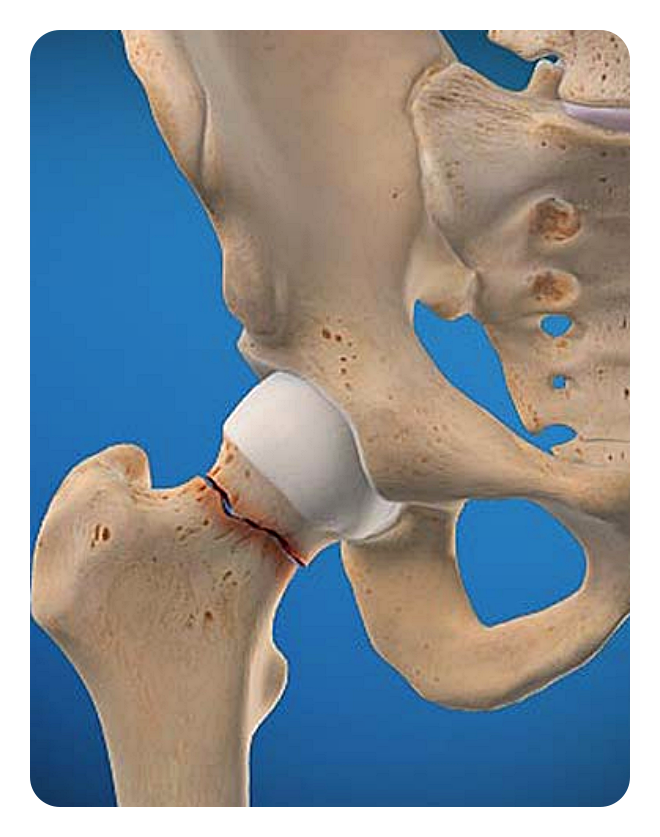

고관절의 골절: 나이가 들어 골다공증으로 뼈가 약해진 경우 고관절 골절이 발생할 수 있습니다. 이럴 때에는 손상된 뼈를 고정하거나, 때로는 인공관절로 대체하는 수술이 필요합니다.

골절 고정술: 골절된 뼈를 원래 위치로 돌려놓고 고정하는 수술입니다. 골절된 부위가 제대로 회복되도록 돕는 중요한 수술입니다.